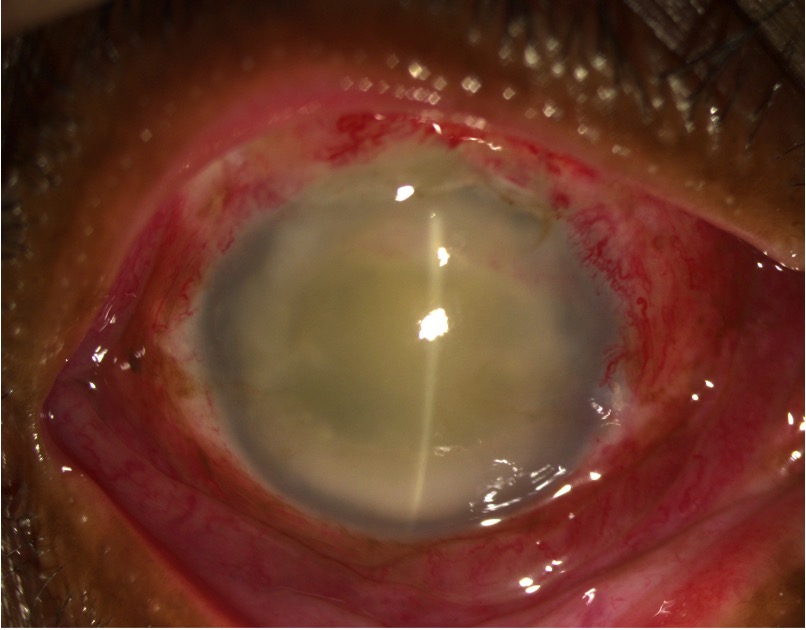

Study Calls for Microbiology-Guided Treatment, Genomic Surveillance in Eye Infections

Hyderabad, Apr 7 (TNT): Researchers from the CSIR-Centre for Cellular and Molecular Biology (CCMB) and the LV Prasad Eye Institute have highlighted the urgent need for microbiology-guided diagnosis, targeted treatment and genomic surveillance in hospitals following a study that found high levels of antimicrobial resistance (AMR) in eye infections.

The researchers found that more than 45 per cent of bacterial isolates from patient samples were multidrug-resistant, including both Gram-positive and Gram-negative pathogens. These included vancomycin-resistant Staphylococcus aureus and extensively drug-resistant Klebsiella pneumoniae.

The study also found resistance to commonly used antibiotics, particularly fluoroquinolones, across all tested eye pathogens, raising concerns over the continued reliance on empirical therapy, where treatment is initiated before laboratory confirmation.

Experts said the findings underline the need for microbiology-based diagnosis and targeted treatment approaches, especially for severe infections such as microbial keratitis and endophthalmitis.

Highlighting the clinical implications, Dr Joveeta Joseph said the findings provide a foundation for developing region-specific treatment guidelines and strengthening antimicrobial stewardship in ophthalmology.

Dr Prashant Garg, Executive Chair, LVPEI , said eye infections reflect the broader AMR landscape in the environment, positioning them as an important site for surveillance.

The researchers emphasised that the study calls for urgent adoption of targeted therapies and strengthened surveillance systems to tackle the growing threat of antimicrobial resistance.